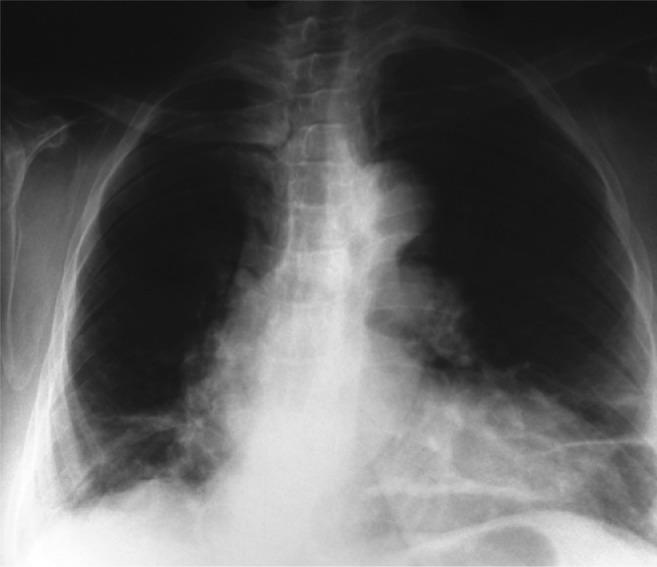

Abnormal chest x-rays were observed in 93% of patients with bronchial anthracofibrosis; patchy consolidation was the most prevalent finding. The most significant CT finding was lymph node calcification (80%, odds ratio = 22.9), followed by bronchial calcification and bronchial stenosis (odds ratio = 6 and 2.91, respectively). Other significant findings were mass-like lesions (14%) and collapse (20%). CT findings were unremarkable in less than 1/6 of subjects.

Lymph node and bronchial calcification can serve as accurate signs in diagnosing anthracosis of the lung. In addition, mass lesions, collapse and infiltration may be associated with a benign course.